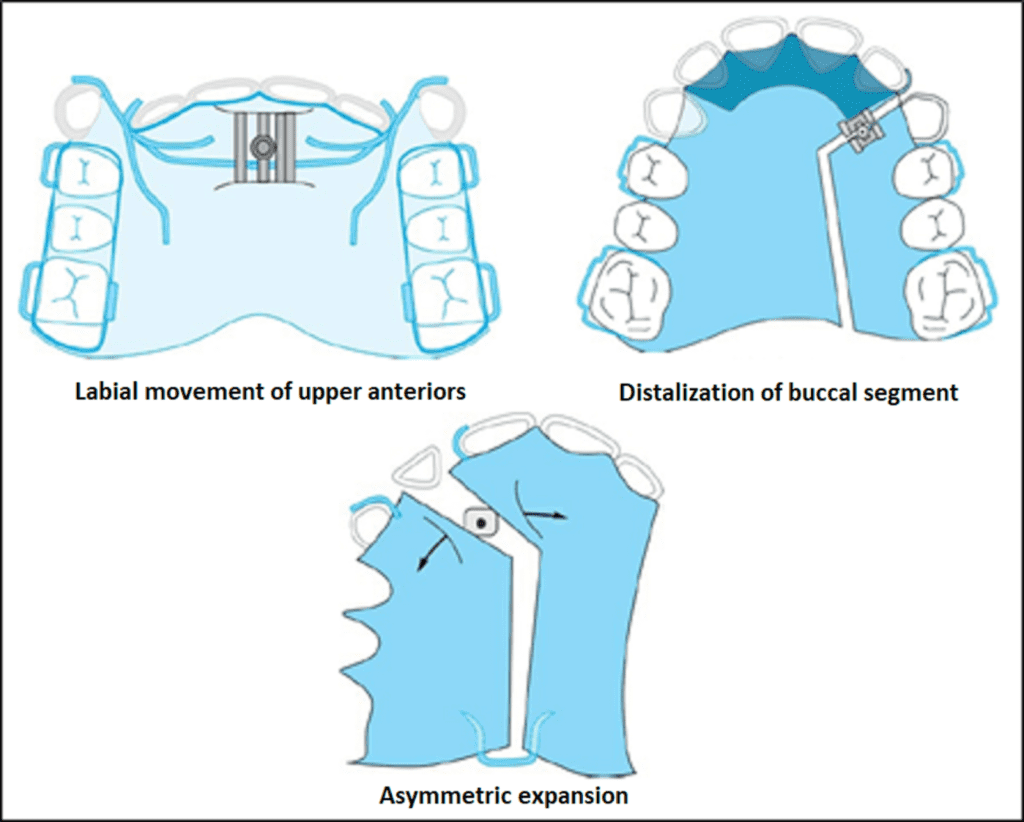

Modifications of expansion plate

Apart from the horizontal placement for transverse expansion, screws can be placed in the following ways:

- Screws are placed in the anterior aspect of the palate parallel to the mid-palatal suture for anterior expansion. E.g., cases of anterior crossbite.

- 2. A ‘Y’-shaped plate will produce simultaneous lateral expansion of posterior teeth and anterior expansion.

- Distalisation of buccal segments can be achieved using expansion screws.

- Expansion plates can be modified for asymmetric expansion.